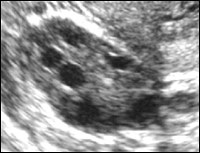

Pentru secreția de fază timpurie sau faza Iuțeală timpurie (zilele 15-18), caracterizată prin apariția la locul de corpus luteum ovulatiei 15-20 mm (de obicei, mai puțin folicul dominant) având o formă neregulată, contururi inegale și extrem de diverse ecostructură interioare diferite grade ecogenicitate (Figura . 14). Acest polimorfism ecografic deosebit de ușor de explicat kernel substratul morfologic al corpului galben, care este un cheag de sânge în diferite grade și liza trombusului [10].